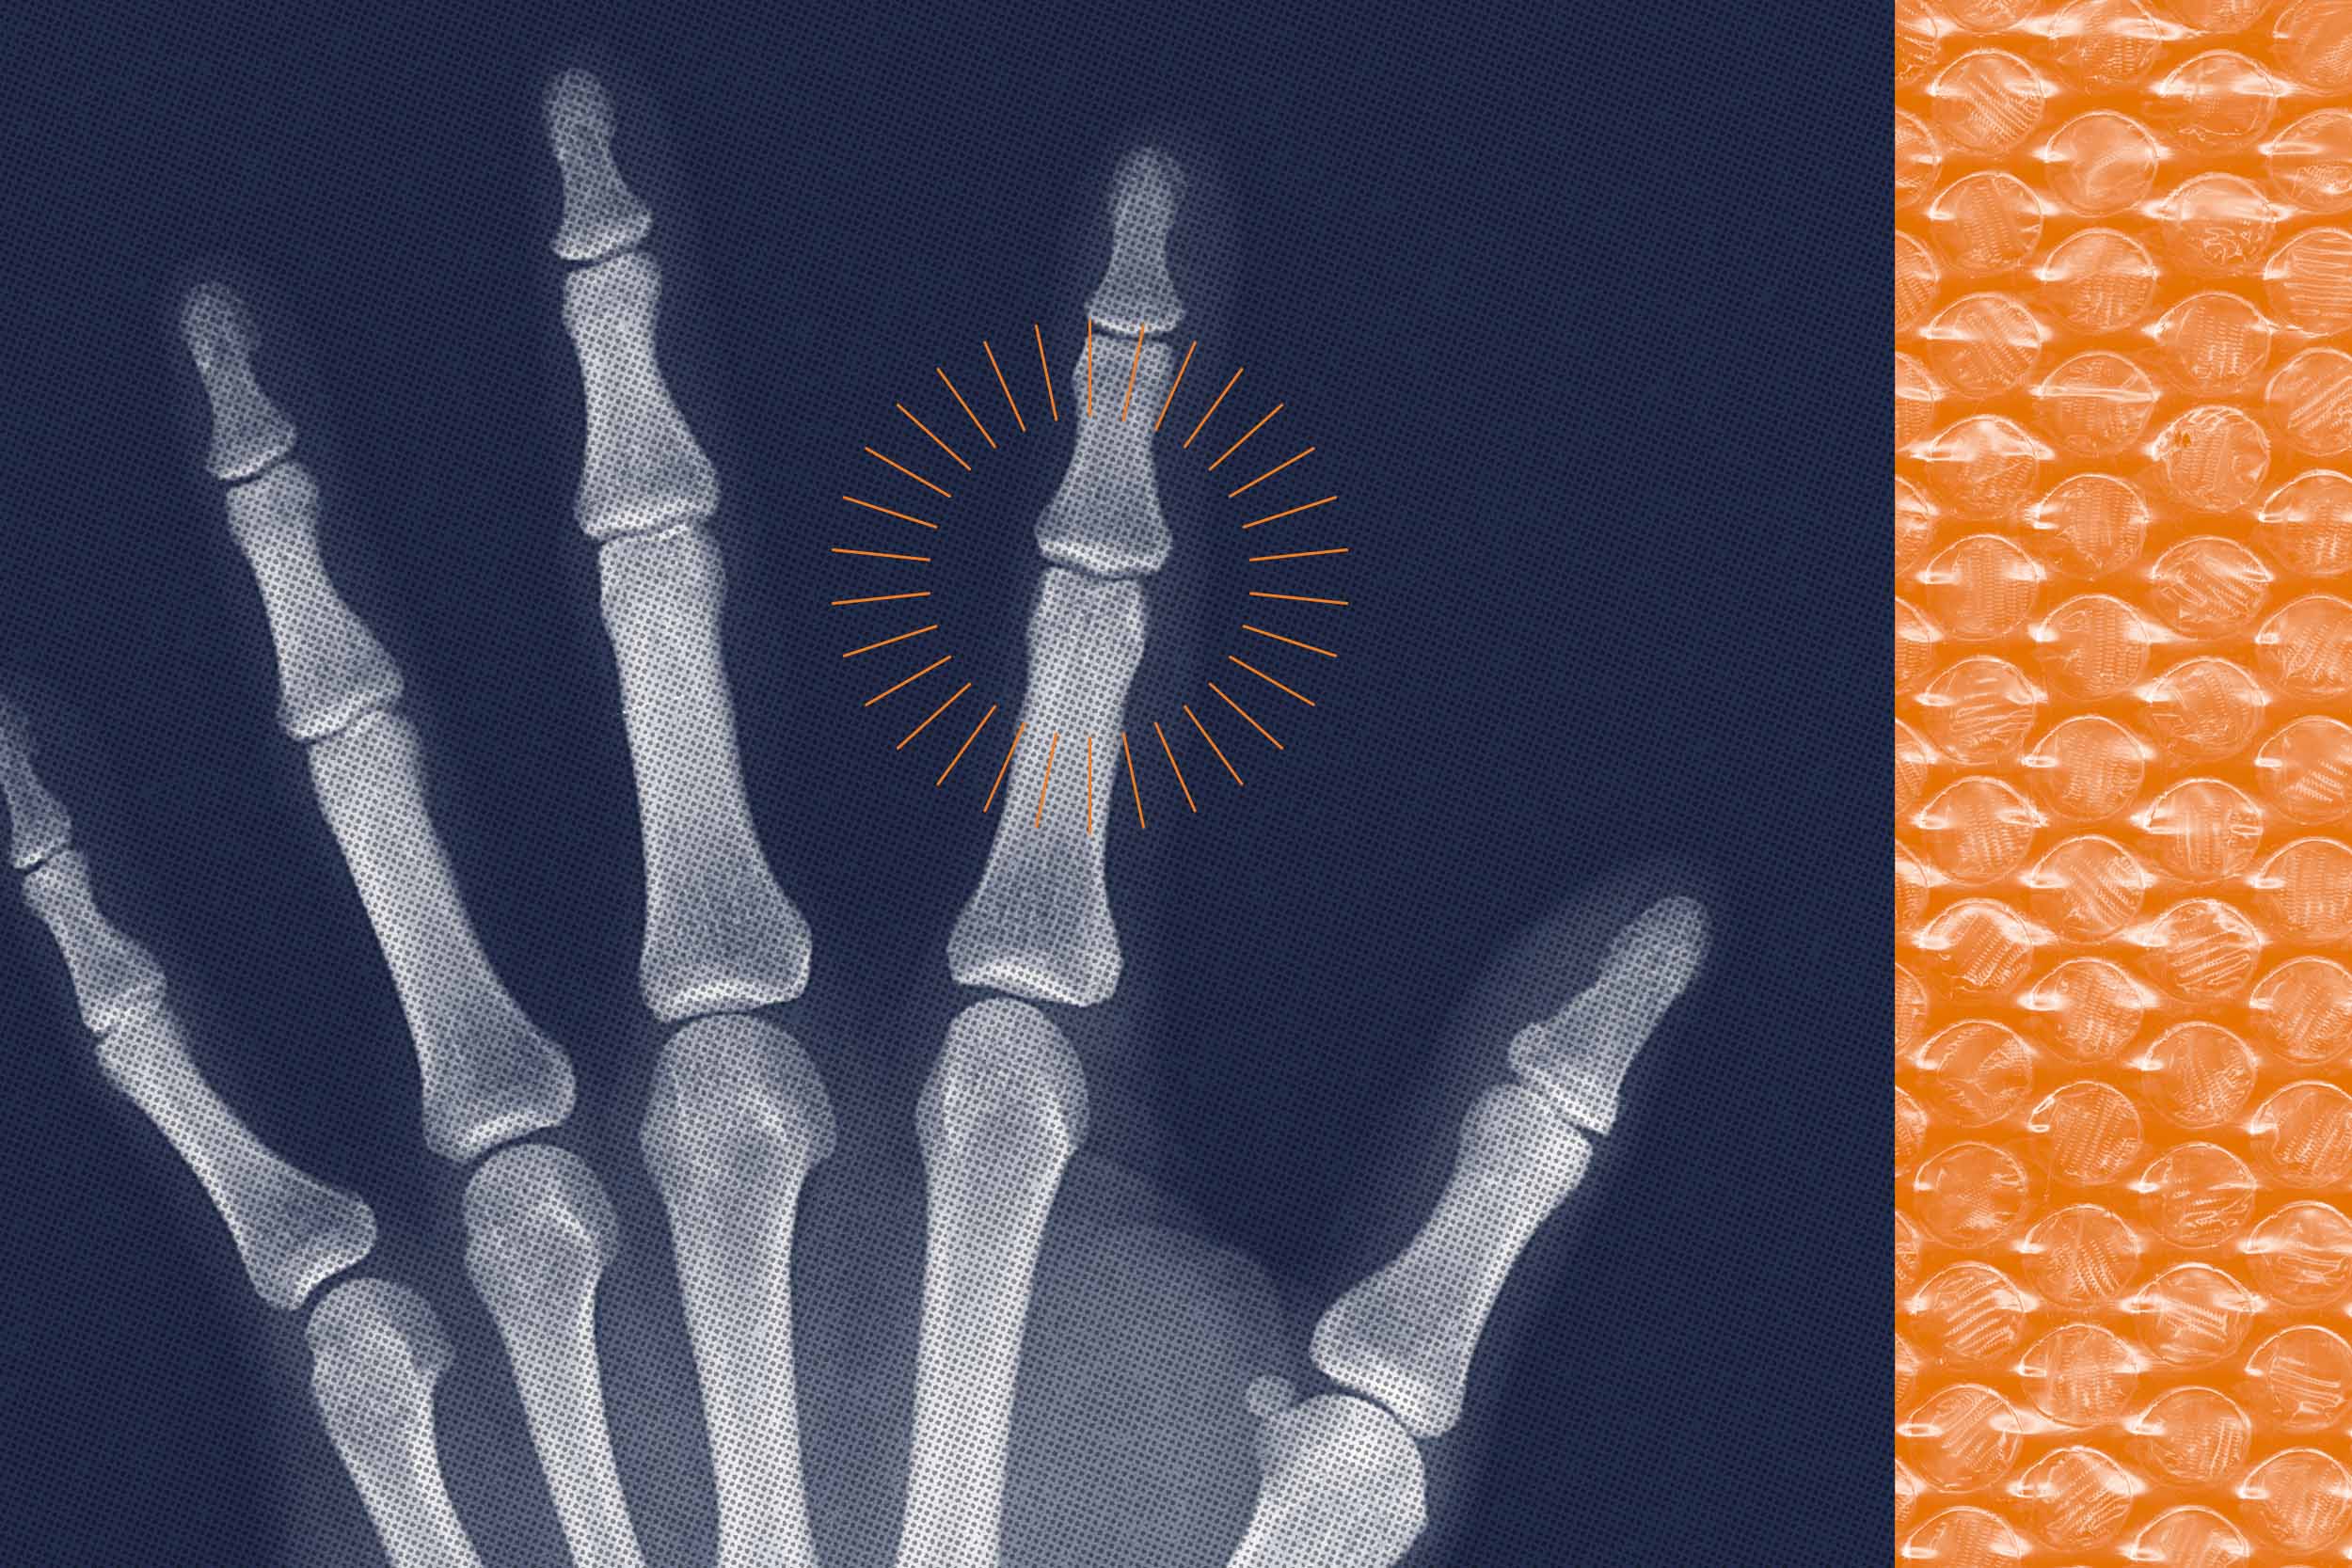

The familiar sound of joints cracking can be heard in many settings, whether it’s the workplace or the comfort of your home. From the subtle pop of a knee in motion to the snap of knuckles, joint noises are a common occurrence.

According to Saliba, two primary factors contribute to the noises joints produce. The first is a phenomenon similar to cracking knuckles, where microscopic gas bubbles exist within the synovial fluid of joints. When a joint is “distracted,” these gas bubbles consolidate and burst due to the negative pressure, resulting in a popping sound. This process, known as cavitation, can offer temporary relief by reducing pressure on joint receptors.

The second cause of joint noise is friction. Bursae, which are fluid-filled sacs, allow smooth movement over bony projections. However, overuse can lead to friction, causing these structures to produce more fluid and swell. Although this friction can be felt, people often continue activities like running or painting, leading to increased friction and swelling. While the pain might subside over time, the popping and clicking sounds may persist.